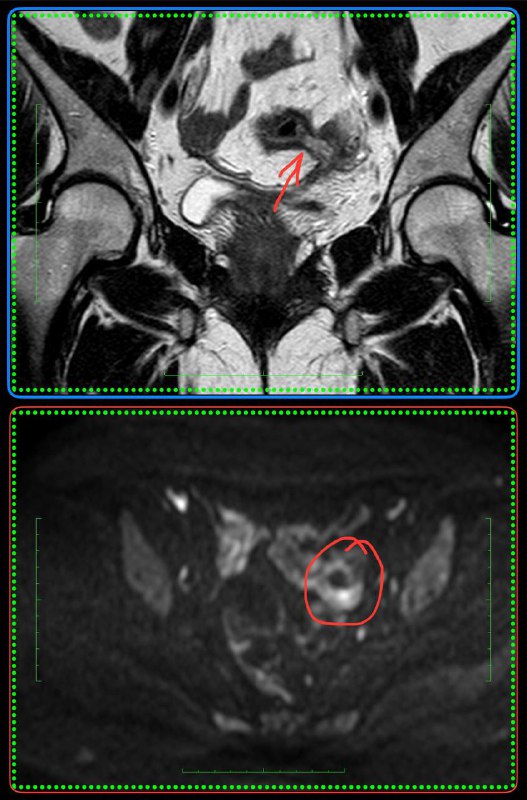

Всем привет!

А вот для чего иногда нужен контраст на МРТ предстательной железы: по DWI, а она является основной последовательностью для оценки периферической зоны, типичные изменения ПИРАЦ-4 (наибольший размер - 12 мм), но вот на Т2 - жидкость, а не серость, и на постконтрастных накопления контраста нет вообще. Так что, это - абсцесс, а не рак.

Соблюдайте протокол и не будете разочарованы.